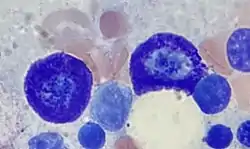

.jpg.webp) |

Macrophage | Monocyte | Macrophage | 20-21 |

|

[8][9] | |

|

Histiocyte | Monocyte | Macrophage |

|

20-21 |

|

[10][8] |

|

Kupffer Cell | Monocyte | Macrophage |

|

20-21 |

|

[11][8] |

|

Alveolar Macrophage | Monocyte | Marcophage |

|

20-21 |

|

[8] |

|

Dendritic Cell | Monocyte | Dendritic Cell |

|

10-15 |

|

[12][13] |